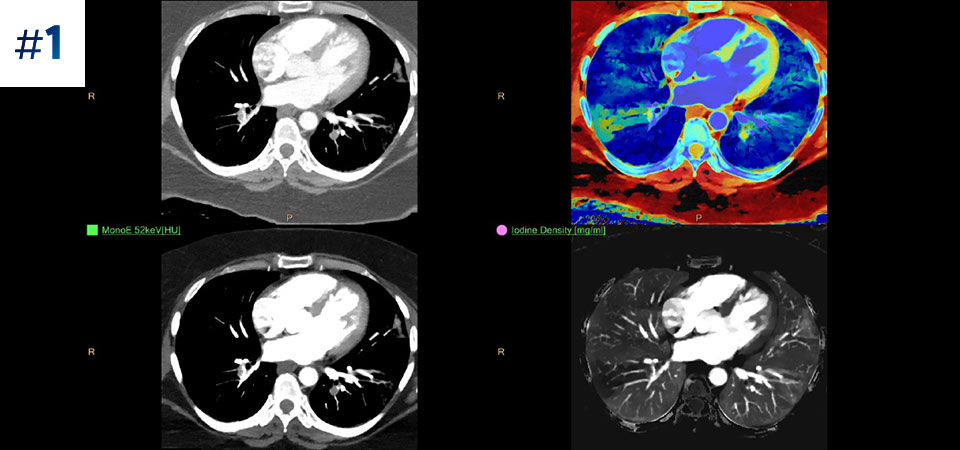

Chest for PE

Go beyond conventional CT. See how layers of spectral-detector results can enhance your diagnostic confidence.